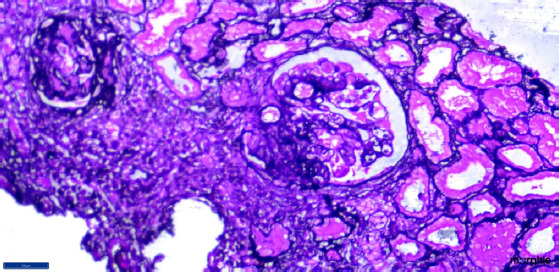

Collapsing glomerulopathy (CG), usually presents with renal dysfunction, hypertension and proteinuria. The etiology is uncertain, yet a number of associations, including many viral infections commonly have been reported. Tuberculosis (TB), one of the most common infections, is not known to cause CG. We report a case of severe renal dysfunction requiring dialysis who had collapsing glomerulopathy on biopsy and evidence of active pulmonary tuberculosis. Anti-tubercular therapy alone resulted in improvement in kidney function.

Abstract Image